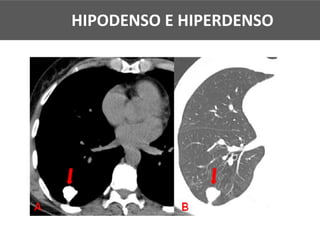

HIPODENSO E HIPERDENSO